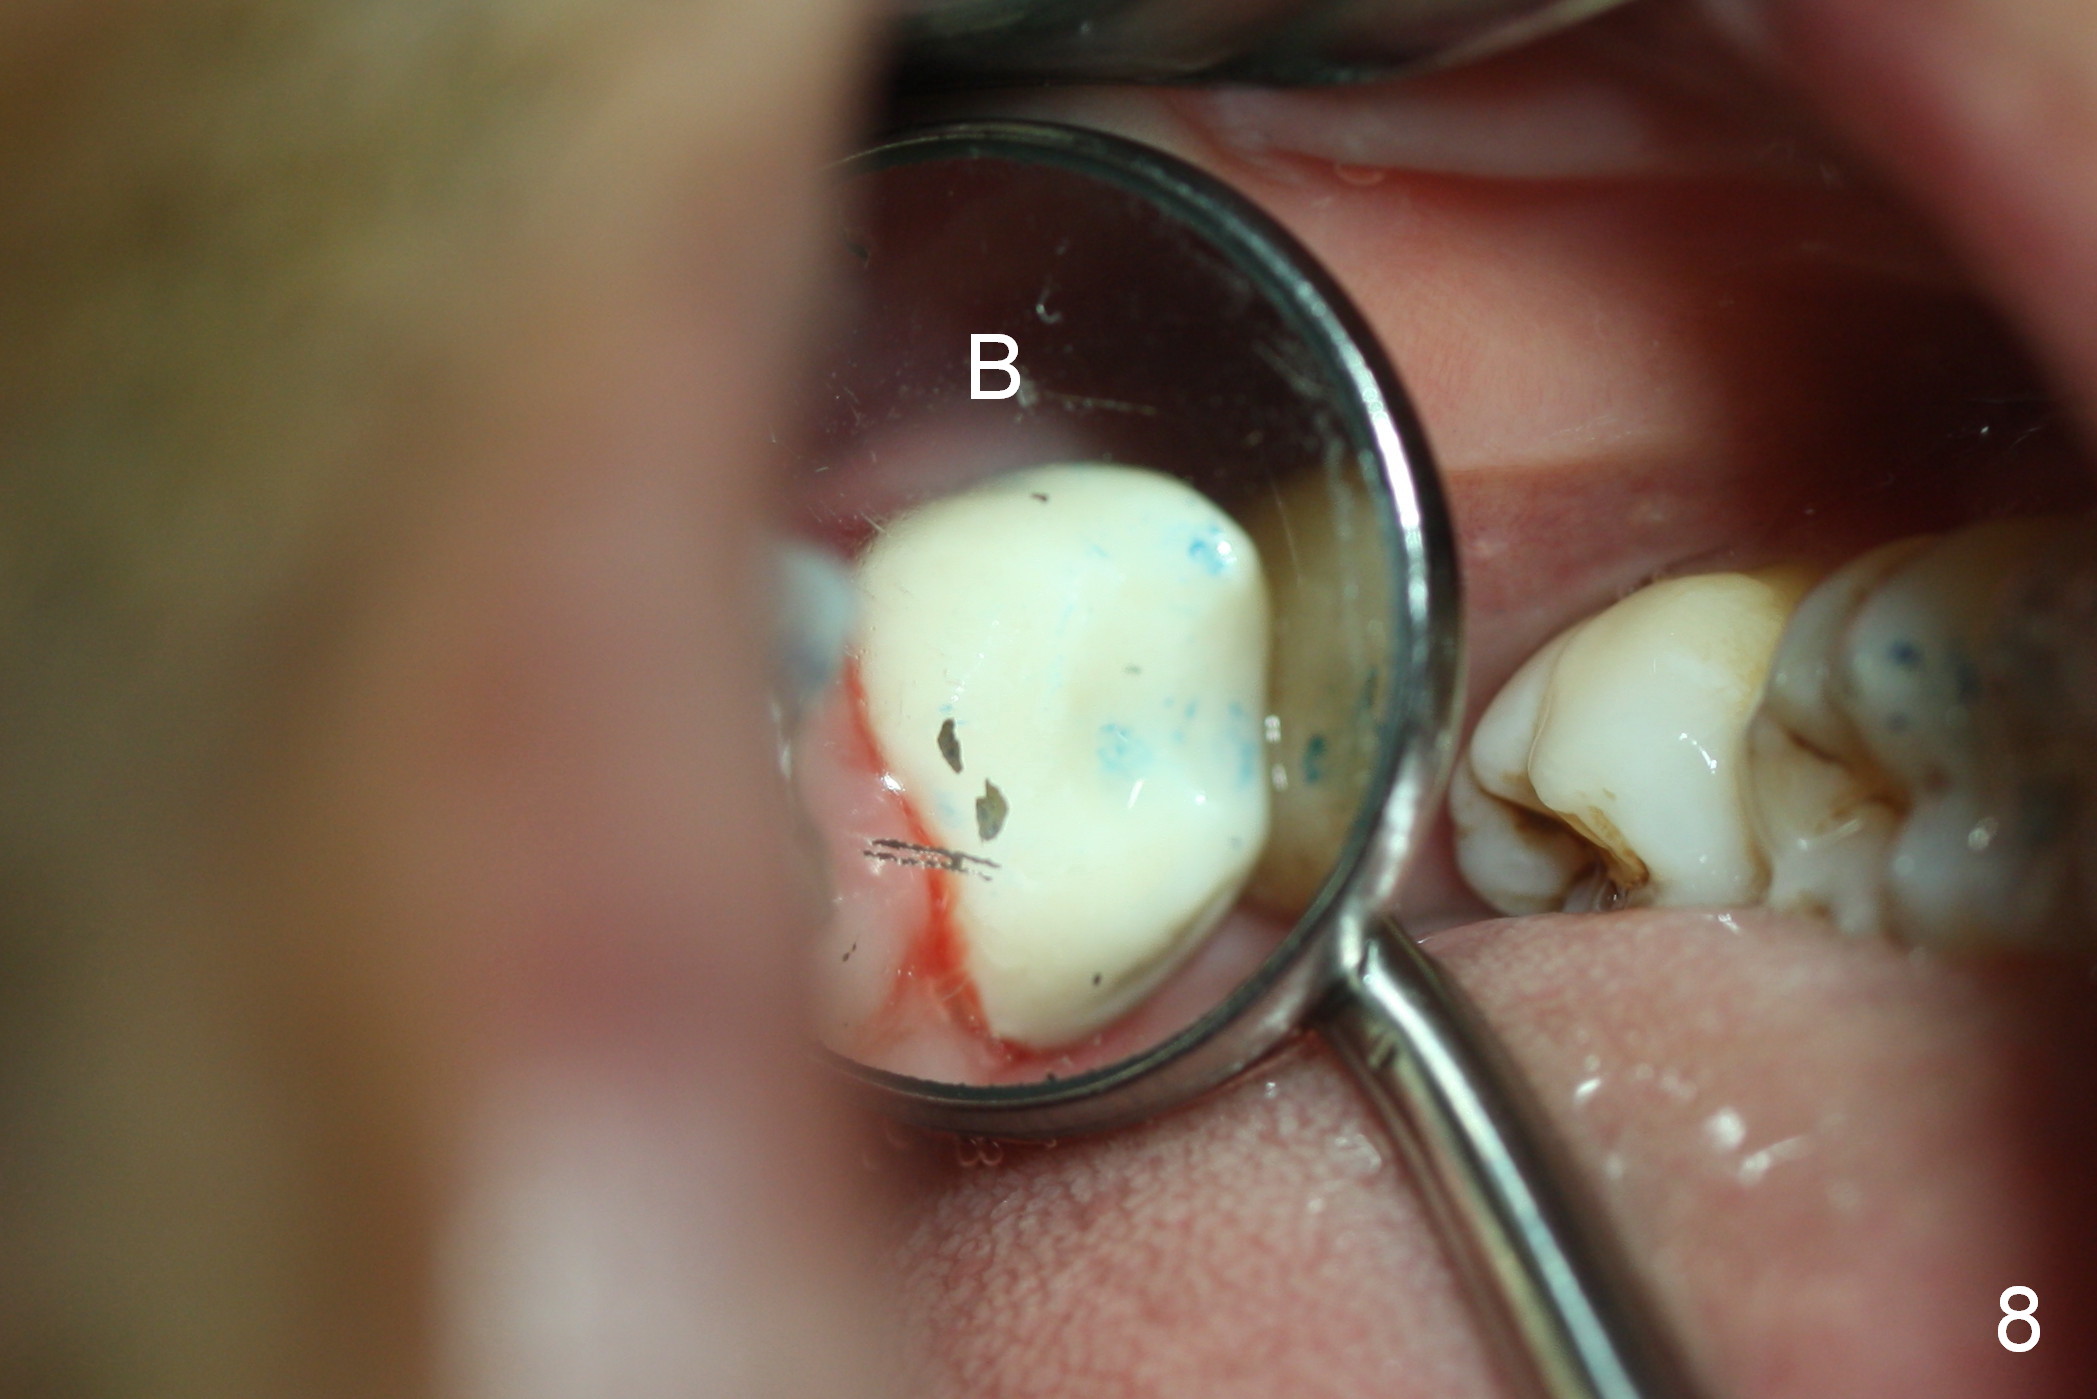

A 50-year-old man (TK) had sign & symptom of crack tooth at #15 (Fig.1) and chose to have root canal therapy done by a specialist. One month later, he returns for crown; exam reveals a crack line mesiodistally (Fig.2). The patient agrees to have immediate implant (Fig.3 design: 6x14 mm). The buccal roots fracture upon luxation. Osteotomy starts in the septum with a 2 mm pilot drill and deviates to the palatal socket, followed by 2, 3, 4 mm tapered osteotomes. A series of taps are placed: 6x17 mm one achieves stability (Fig.4). When the latter is removed, there is no sign of sinus air leakage. A 6x14 mm implant (Fig.5 I) and a 5x3 mm abutment (A) are placed. After abutment height adjustment, an immediate provisional is fabricated. Allograft with Osteogen is placed in the remaining sockets and gaps (Fig.6 *). Fig.7 shows the inner side of the provisional with double arrows indicating the dimension of the abutment, whereas arrowheads the dimension of the socket buccopalatally. When the provisional is cemented (Fig.8 P), it completely seals the socket. As long as the provisional stays, bone graft will not be lost.